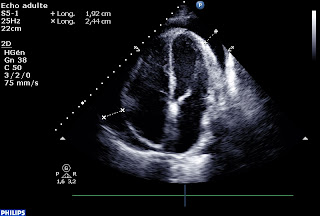

Même si il est difficile de sortir un échographiste de son rôle de contemplateur, c’est possible. Après avoir injecté quelques bulles pour s’assurer d’être dans le péricarde, on passe un guide métallique (pas trop loin le guide, Nico, stp…)

Et on draine. En fin de procédure, on laisse le drain en place pour le liquide restant.